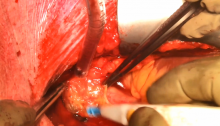

The right atrium was opened and stay sutures were used to facilitate atrial septum exposure. Through the incision of the fossa ovalis, the mass insertion to the interatrial septum was identified and a traction suture was applied. By means of careful dissection, the atrial myxoma was removed and the zone of attachment excised. During the entire open heart surgery, carbon dioxide was delivered in the operative field.

The tumor appeared as a voluminous mass of about 6 cm in length with a gelatinous apparence; on its surface, yellowish and hemorrhagic areas were present. The presence of additional tumors was excluded after removing a little remnant, and the left atrium was irrigated with saline solution. The endocardium was sutured directly with no need of pericardial patch, and the septum was closed. In this case, the interatrial approach was feasible because of the tumor connection towards the anterior mitral annulus. Otherwise, a biatrial access could be the alternative choice. After a proper deairing of the left chambers, the aortic clamp was removed and the right atrium closed.